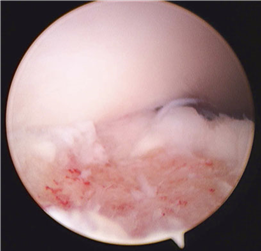

Clinical & Radiographic Imaging Archive